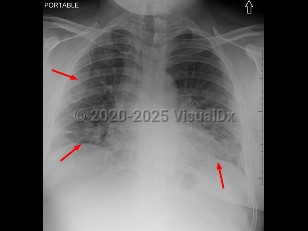

Sore throat, Neck mass, 50-59 year old Female

Lemierre syndrome